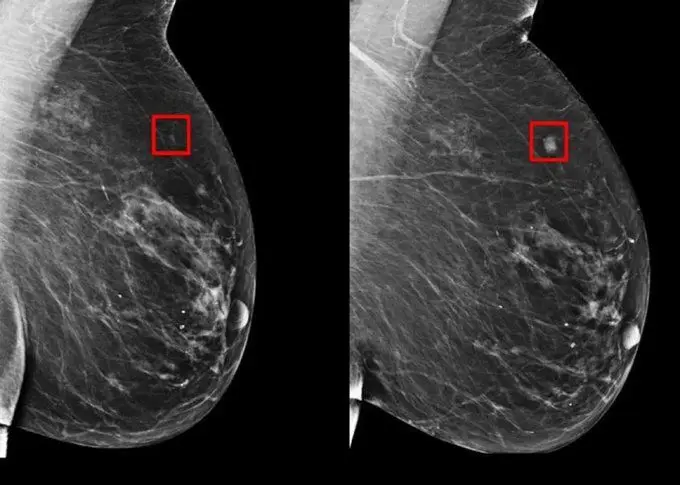

Traditional risk models, like Tyrer‑Cuzick, rely on family history and clinical factors. Mirai takes a different approach:

- It uses deep learning to analyze mammograms directly.

- It was trained on over 2 million images. (NAM)

- It can predict personalized five‑year cancer risk, across age groups, races, and breast densities.

- Unlike older tools, it does not require patient history.

By uncovering subtle imaging patterns, Mirai detects risks long before traditional models can. (WIRED)